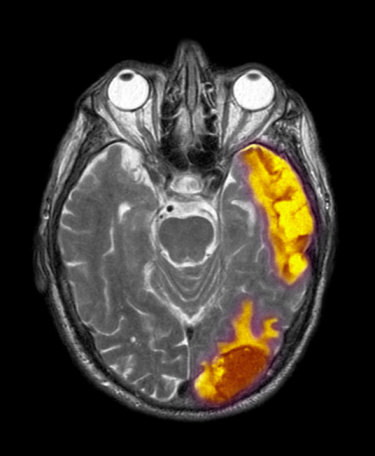

视力障碍:颅内压增高时会使眼球静脉血回流入脑不畅而淤血水肿,损伤眼底视网膜上的视觉细胞,致视力下降,严重时眼底视网膜有点状、线状、片状,甚至有火焰状出血,视物模糊,更重时会因压迫损伤视神经引起失明。